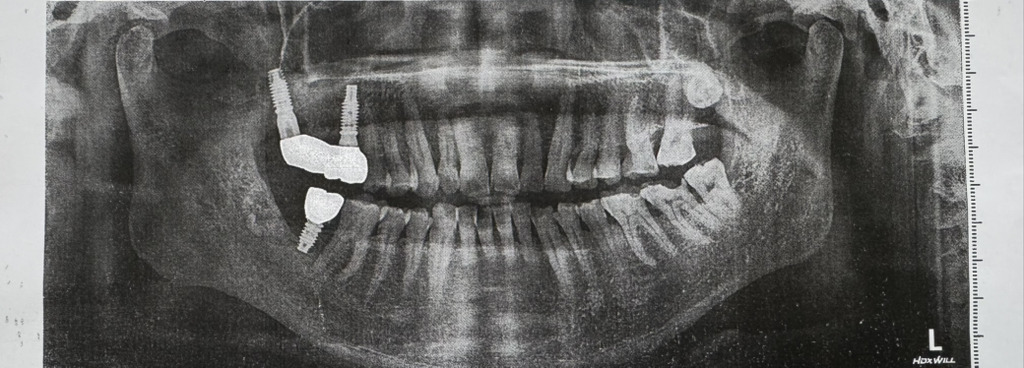

사랑니 포함 발치 5개 했고 임플란트 처음에 3개 심었는데 그중 하나가 뿌리가 제대로 고정안되여서 뽑고 3개월만에 다시 심었어요.근데 기존에 심었던 어금니 자리 아니고 사랑니 자리에 사선으로 심었고 사전에 그 어떤 상담과 상의도 없이 그대로 임플란트 마무리 했줬어요.사진 한번만 바주세요.이렇게 임플란트 하는 경우도 있나요?